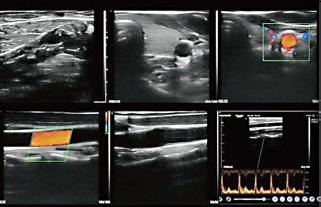

Sisteme cu ultrasunete ultraportabile

• Cele mai portabile dispozitive cu ultrasunete: reduce aparatul tradițional cu ultrasunete într-un traductor.

• Ușor de manevrat, oferă o interfață cu ultrasunete intuitivă, puteți opera cu ușurință pe dispozitivele dvs. inteligente (telefon/tabletă/PC).

• Consum redus de putere, tehnologia de procesare a imaginii vă poate oferi o imagine de calitate.

• Sistem de operare și aplicație pentru Android / Windows / IOS

Aplicații: abdomen, părți moi, vascular, cardiologie, obstetrică ginecologie, urologie, MSK, urgențe, pediatrie, pulmonar, etc.

Sistem ecograf ultraportabil scanare liniară

Aplicații: părți moi, vascular, musculoscheletal, point-of-care (POC), urgențe, medicină sportivă

• Cap liniar L45/ L25

• Conectare wifi

• Doppler color

• IOS, Android and windows

• Moduri B, B/M, color, PW, PDI

• Nuanțe gri 256

• Frecvențe sonde: L25 - 10-14 mhz, L45 – 7,5-10 mhz

• Adâncime scanare: L25 - 20-80mm, L45 - 20-100mm

• Număr canale 64

• Frame-uri 24s/f

• Acumulator

• Geantă transport

• Încărcător wireless